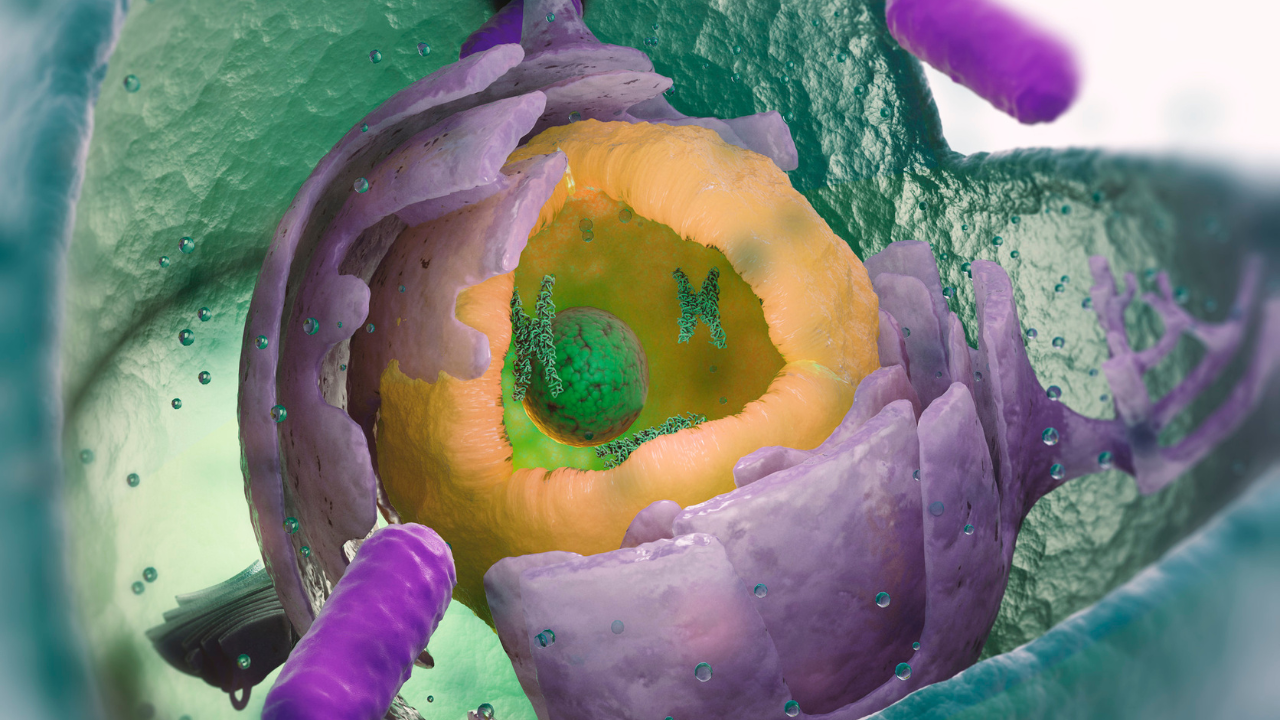

What is the main mechanism behind Maltodextrin’s damage?

The research shows that the key mechanism behind this damage appears to be linked to stress on the endoplasmic reticulum (an important organelle found in the eukaryotic cells). When this system is overburdened, it triggers a stress response that contributes to tissue damage and inflammation. Surprisingly, when researchers treated mice with the same medication to reduce this stress, the inflammation and mucus depletion were significantly reduced.